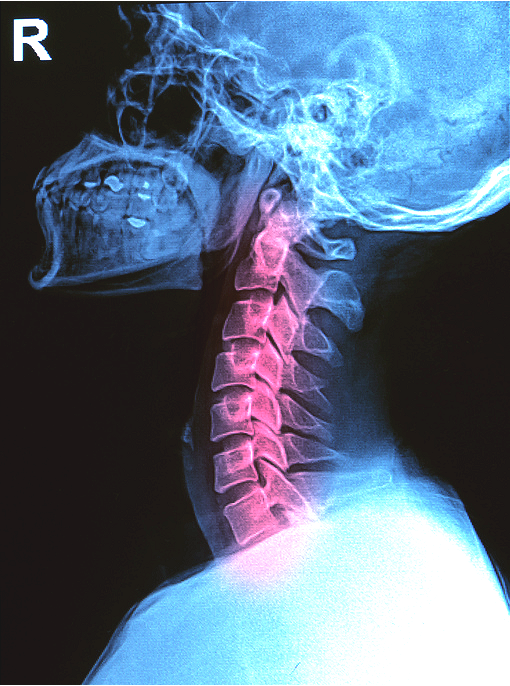

Pourquoi ma tête est trop en avant

et comment ChiropracticBioPhysics® peut m’aider à y remédier?

La posture de la tête projetée en avant ou « Textneck» ...